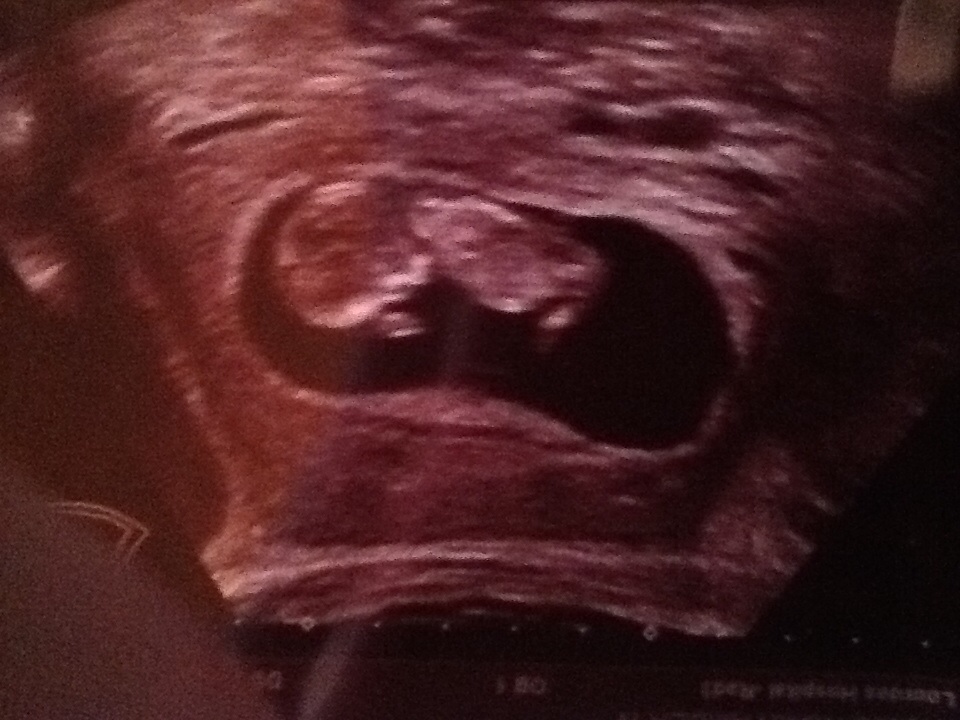

My 12 week ultrasound, can you tell the sex!?!

No nub :(